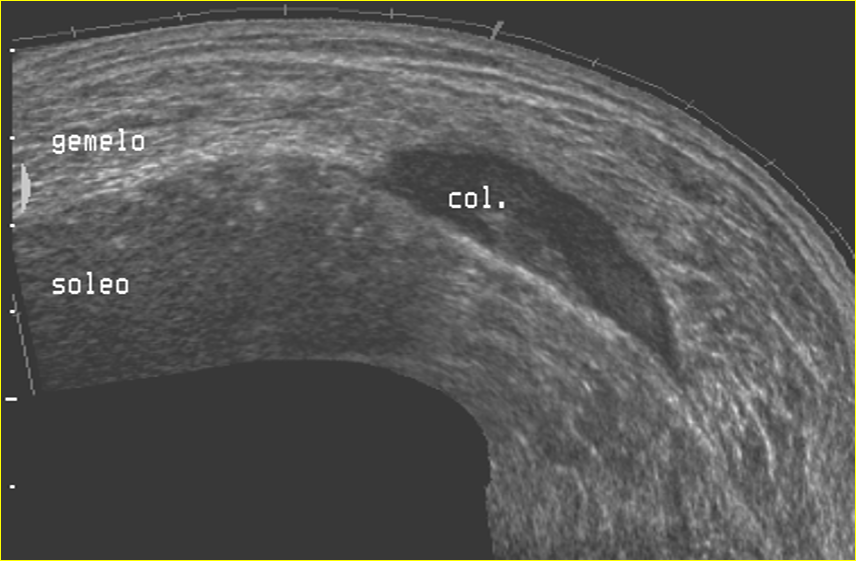

Interpretación especializada del sistema osteomioarticular

Nos enfocamos en la interpretación de ecografías de , tendones, músculos y articulaciones, lo que nos permite detectar con precisión cualquier anomalía o lesión en estas áreas.